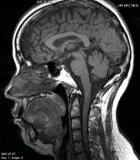

MRI画像

脳動脈瘤 早期の脳硬塞 頭部縦断面

腹部 腰椎 頚椎

MRI検査は、様々な部位の検査ができます。

特に頸椎・腰椎などの椎間板ヘルニア、関節、胆嚢の形姿観察などが得意分野です。